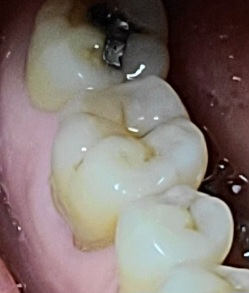

가능하다면 치과에서 가서 하고 싶어서요. 치아에 검고 가늘게 거미처럼 보이는데 아프거나 어떤 이상도 없지만 그대로 두면 충치로 진행되는게 아닐까 걱정 되네요.

사진 첨부

• 1번 째 사진

1. 이미 충치가 생긴 상태에서는 실란트를 하지 않습니다.

2. 지금의 경우 정확히 실란트라고 하는 진료보다는 초기 충치에 대해 갈아내고 해당 부위를 얇게 레진으로 떼우는 최소침습법 치료가 있습니다.

3. 다만, 현재 씹는면 외에도 첫번째 큰 어금니, 두번째 큰 어금니 사이의 충치도 육안으로 의심되기 때문에 방사선 사진 찍어 확인을 해봐야 합니다 내부가 썩어 있을 수도 있습니다